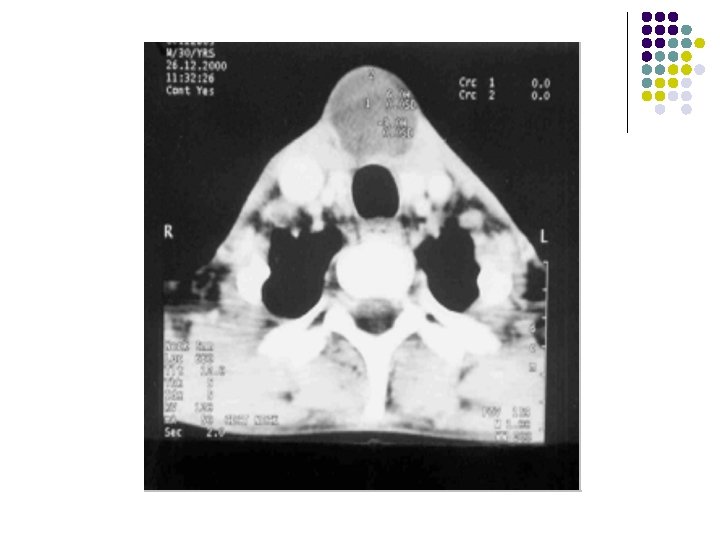

Findings: l Soft tissue density lesion in midline below the level of hyoid bone embedded within the strap muscles.

IMAGING FEATURES: l On ultrasound, they appear as hypoechoic masses with few septae and internal echoes. l CT scan : They are hypodense and well defined with minimal enhancement of the margins on contrast scans. l MR can also be used for superior soft tissue evaluation. The lesions are hypointense on T 1 W images and hyperintense on T 2 W images. l l These lesions usually lie medial to the sternocleidomastoid muscle, anterior to the carotid sheath and lateral to the thyroid gland.

IN OUR PATIENT… l l Midline ant. Neck mass which moves on protrusion of toungue. Anechoic cystic lesion in infrahyoid region with beak extenmding in suprahyoid region on usg. on. Ct. . Low density lesion with mininmal rim enhancement and in classical location. DIAGNOSIS: THYROGLOSSAL CYST